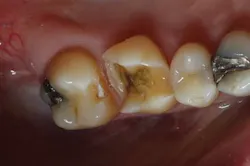

Figure 5: Bitewing x-ray shows no indication of caries on tooth No. 2Before I began prepping for the crown, I used CariVu. On the images, I saw not only a crack on the tooth that was to be crowned, but also clear caries on the adjacent tooth (figure 6). During treatment, I snapped a picture of the preparation on tooth No. 2 with an SLR extraoral camera (figure 7). I took an additional photo mid-treatment to show how far the cavity had progressed into the dentin. The bitewing didn't show any of this decay. This caries detection technology gives me a great opportunity to tell patients that I found a cavity that we would not have known about until it caused trouble. There is no surprise later and no apologies for missing an early lesion.

Figure 6: CariVu image clearly shows mesial decay on tooth No. 2While some incipient lesions can be put on a "watch list," some should be treated early. Patients don't want to wait until they are in pain or having sensitivity, and that can be avoided by detecting and restoring caries early with smaller fillings that last longer and are less damaging to tooth structure. CariVu has given me another way to prove that I have confidence in my diagnoses. When I have shown x-rays to patients in the past, some have said, "I don't see it, but I trust you." I appreciate their trust, but what I really enjoy is being able to show proof of the caries, treat it, and then follow through.